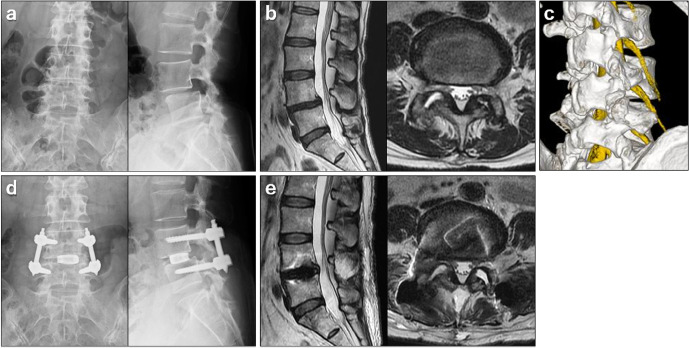

前言:比较采用经皮内镜下经椎间孔腰椎椎间融合术(PETLIF)系统的全内镜下经椎间孔入路腰椎椎间融合术(TF-LIF)和微创经椎间孔腰椎椎间融合术(MIS-TLIF)的临床结果。方法:共102例患者,其中女性80例,男性22例;平均年龄:70.0岁)的退行性腰椎疾病患者接受PETLIF治疗并随访2年,被分配到PETLIF组。根据PETLIF组的年龄、性别和手术腰椎水平,100例患者(71例女性,29例男性;随机选择接受MIS-TLIF的患者纳入MIS-TLIF组,平均年龄68.9岁。这项回顾性调查包括手术资料、影像学评估和临床结果。结果:PETLIF组和MIS-TLIF组融合率分别为95.1%和96.0% (P=0.38)。PETLIF组术前至术后1天血红蛋白水平的下降明显低于MIS-TLIF组(ppp)结论:与MIS-TLIF相比,PETLIF具有良好的骨融合率和临床效果。它是微创的,导致较少的失血。然而,出神经根损伤是petlifs特有的并发症,需要适当的预防管理,包括扩大Kambin三角区的技术。

Methods: A total of 102 patients (80 females, 22 males; mean age: 70.0 years) with degenerative lumbar spine disorders who underwent PETLIF and were followed up for 2 years were assigned to the PETLIF group. Based on age, sex, and operated lumbar levels in the PETLIF group, 100 patients (71 women and 29 men; mean age: 68.9 years) who underwent MIS-TLIF were randomly selected and included in the MIS-TLIF group. This retrospective investigation included surgical data, radiographic assessment, and clinical outcomes.

Results: The fusion rate was 95.1% and 96.0% in the PETLIF and MIS-TLIF groups, respectively (P=0.38). The decrease in hemoglobin levels from before surgery to 1 day after surgery was significantly lower in the PETLIF group than in the MIS-TLIF group (P<0.01). Five patients had detectable transient neurologic disorders after PETLIF that were resolved within 3 months. The increase in the local lordosis angle from before surgery to the final follow-up was significantly higher in the MIS-TLIF group than in the PETLIF group (P<0.01). Clinical scores were comparable between the two groups.

Conclusions: Compared with MIS-TLIF, PETLIF showed excellent bone fusion rate and clinical outcomes. It was minimally invasive, resulting in less blood loss. However, exiting nerve root injury was a PETLIF-specific complication, and proper preventive management, including techniques to enlarge the Kambin's triangle, is required.